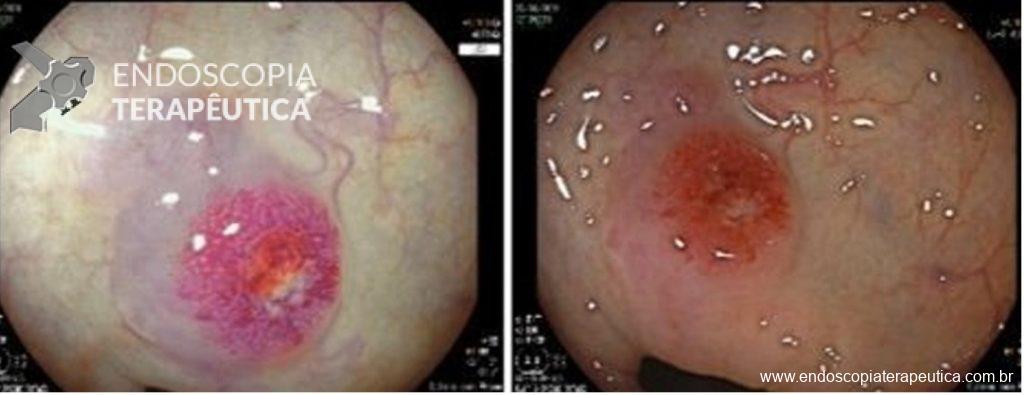

Paciente do sexo feminino, 59 anos, com histórico de enterorragias de repetição, com necessidade de hemotransfusões, apresentando Hb 9,0 mg/dl. A paciente foi submetida a colonoscopia e TC de abdome com o achado de uma ectasia vascular na topografia do cólon descendente (Figuras 5 e 6). A paciente não relatava uso recente de AINEs.

Optado por uma primeira tentativa de abordagem da ectasia vascular com uso de clipe endoscópico convencional sem sucesso, com recidiva do sangramento. Optado, então por tratamento de resgate usando o clipe tipo “over the scope” Padlock (vídeos). O tratamento foi bem sucedido e houve recuperação dos níveis de hemoglobina sem recidiva do sangramento no período de seguimento (15 meses).